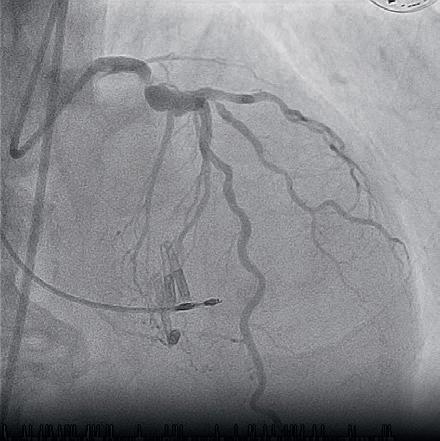

Patients undergoing transcatheter aortic valve implantation (TAVI) do not benefit from the continuation of oral anticoagulation compared to those whose anticoagulants were interrupted before the procedure, new research has shown.

THIS WAS AMONG THE FINDINGS OF the POPular PAUSE TAVI trial, an open-label, investigator-initiated, non-inferiority trial in patients receiving oral anticoagulation undergoing TAVI, comparing the two anticoagulation strategies. Results of the trial were presented at the 2024 European Society of Cardiology (ESC) congress (30 August–2 September, London, UK) and published in The New England Journal of Medicine

At ESC 2024, Dirk-Jan van Ginkel (St Antonius Hospital, Nieuwegein, The Netherlands), on behalf of the POPular PAUSE TAVI investigators, reported that the trial’s primary endpoint—a composite of cardiovascular mortality, stroke, myocardial infarction (MI), major vascular complications and major bleeding—occurred at 30 days in 16.5% of patients who continued oral anticoagulation during TAVI, compared to 14.8% of patients whose oral anticoagulation regime was interrupted.

The risk difference of 1.7% between the two strategies in favour of the interruption group meant that the trial’s non-inferiority margin was not met, hence POPular PAUSE TAVI investigators suggest that their data support the interruption of oral anticoagulation during TAVI.

“The current population undergoing TAVI is different than, for example, the PCI [percutaneous coronary intervention] population,” Van Ginkel said. “These patients are generally older, they have more comorbidities, for example, renal disease, peripheral arterial disease, and cerebrovascular disease. Also, larger catheters are needed to perform TAVI.”

“When such patients using oral anticoagulation undergo a high bleeding risk procedure, such as TAVI, general guidelines on perioperative anticoagulation management recommend interrupting oral anticoagulation for a couple of days,” he noted. Whilst this has been assessed in some observational studies, which have shown a potential decrease in the risk of stroke, without an increase in bleeding when oral anticoagulation was continued, there have been no randomised trials to compare the two strategies in patients undergoing TAVI.

Taking place in 22 European centres, POPular PAUSE TAVI saw 858 patients randomised 1:1 either to continue or stop oral anticoagulation at least 48 hours before their TAVI procedure. The mean age was 81 years and 34.5% were women, 81.9% were taking direct oral anticoagulants, with 18.1% taking vitamin k antagonists.

Secondary endpoints, including cardiovascular mortality, risk of thromboembolic events and ischaemic stroke were comparable between the groups, Van Ginkel noted, but bleeding events occurred in 31.1% of patients in the continuation group and 21.3% in the interrupted group.

“There was no advantage of continuing oral anticoagulation compared with interruption in patients undergoing TAVI with a need for anticoagulation and there was more bleeding in the continuation group,” he said. “Therefore, we think that this trial provides the first randomised data which support interruption of anticoagulation in patients undergoing TAVI.”